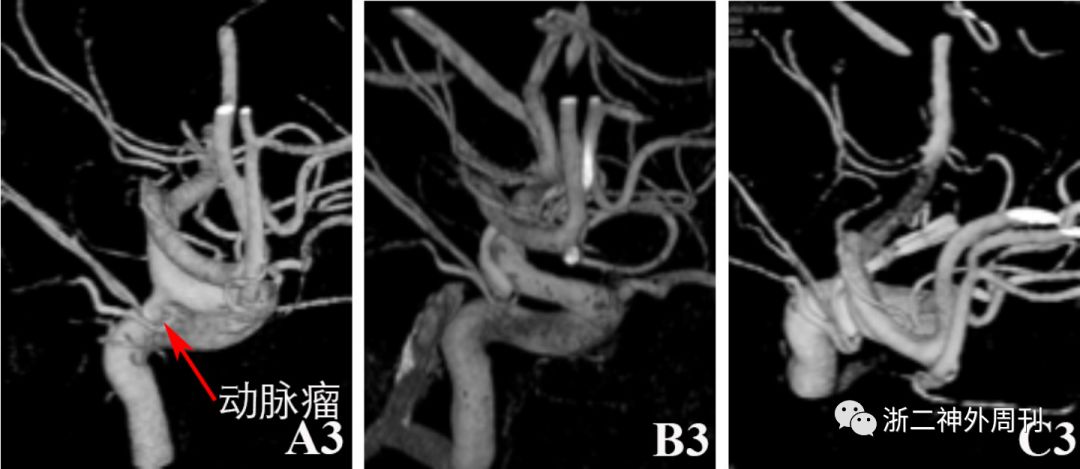

科室讨论,手术指证明确,建议开颅手术并告知手风险等,家属选择开颅夹闭手术。完善术前准备后,采用左侧眶上外侧入路开颅“左侧颈内动脉脉络膜前动脉段动脉瘤夹闭术”,手术过程顺利,术后患者恢复良好。无肢体活动障碍,无眼球结膜充血及颅内杂音等。术后4天常规复查DSA,提示动脉瘤夹闭满意,未见残留。但发现左侧海绵窦硬脑膜动静脉瘘,左侧脑膜垂体干动脉供血,瘘口位于左侧海绵窦后部,双侧岩下窦引流,静脉窦血流方向正常,无皮层静脉引流,诊断为I型左侧海绵窦后部硬脑膜动静脉瘘(图1B1-B3)。因无症状,建议患者密切随访观察,定期复查。期间患者一直无眼球结膜充血及颅内杂音等相关症状体征。8月后再次入院复查DSA,提示动脉瘤无复发,同时硬脑膜动静脉瘘消失(图1C1-C3)。

图1. A1-A3 术前DSA检查提示左侧颈内动脉脉络膜前动脉段动脉瘤;B1-B3:术后4天复查DSA提示动脉瘤夹闭满意,无残留;同时发现左侧海绵窦硬脑膜动静脉瘘,左侧脑膜垂体干动脉供血,瘘口位于左侧海绵窦后部,双侧岩下窦引流,静脉窦血流方向正常,无皮层静脉引流。C1-C3: 随访观察8月后复查DSA提示动脉瘤无复发,硬脑膜动静脉瘘消失。

本例患者的dAVF向双侧岩下窦引流,静脉窦引流方向正常,无皮层静脉引流,因此诊断为I型dAVF。患者术后恢复良好,无dAVF相关症状,系常规复查DSA时偶然发现。考虑到I型dAVF一般预后良好,我们采取密切随访观察,术后8月再次复查DSA提示dAVF完全消失。文献中尚无类似情况报道。